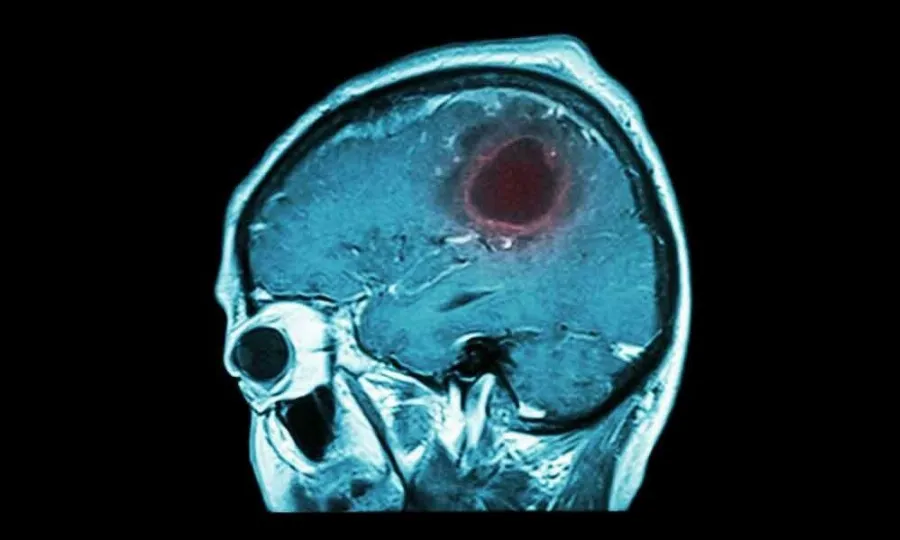

Όγκοι εγκεφάλου: Συμπτώματα και σύγχρονη αντιμετώπιση

Οι όγκοι εγκεφάλου αποτελούν ένα από τα πιο συνήθη προβλήματα της νευροχειρουργικής. Μια πολύ απλή και ταυτόχρονα βασική διάκρισή τους είναι σε πρωτοπαθείς, που προέρχονται από τον ίδιο τον εγκέφαλο και τα περιβλήματά του, και σε δευτεροπαθείς, αυτούς που ουσιαστικά προέρχονται από όγκους που βρίσκονται σε άλλο σημείο του σώματος. Εξίσου σημαντική είναι η διάκρισή των πρωτοπαθών όγκων σε καλοήθεις και κακοήθεις, ενώ οι δευτεροπαθείς είναι εξ ορισμού κακοήθεις.

Όγκοι εγκεφάλου: Πώς καταλαβαίνω ότι υπάρχει περίπτωση να έχω;

Το συχνότερο σύμπτωμα των όγκων εγκεφάλου είναι ένα σταδιακά επιδεινούμενο νευρολογικό έλλειμμα, όπως αδυναμία ενός άκρου, πρόβλημα στη κατανόηση ή εκφορά λόγου (δυσφασία), αλλά και ο επιδεινούμενος πονοκέφαλος, μειωμένο επίπεδο συνείδησης, επιληπτικές κρίσεις κα. Ειδικά οι όγκοι υπόφυσης μπορούν να εκδηλωθούν με ενδοκρινολογικές διαταραχές. Πολλές φορές, οι όγκοι εγκεφάλου είναι τυχαία ευρήματα σε απεικόνιση για άλλο λόγο.

Όγκοι εγκεφάλου: Ποιες εξετάσεις χρειάζεται να γίνουν;

Συνήθως η αρχική διάγνωση γίνεται με αξονική τομογραφία, αλλά τις περισσότερες φορές για τον πλήρη χαρακτηρισμό μια βλάβης απαιτείται μαγνητική τομογραφία με ενδοφλέβιο σκιαγραφικό και ίσως ειδικές ακολουθίες. Κάποιες φορές (όπως σε όγκους υπόφυσης) αιματολογικές εξετάσεις είναι απαραίτητες. Τέλος, σε ορισμένες περιπτώσεις απαιτείται ακόμα και βιοψία της βλάβης, με την τελική διάγνωση να δίνεται από τον παθολογοανατόμο.